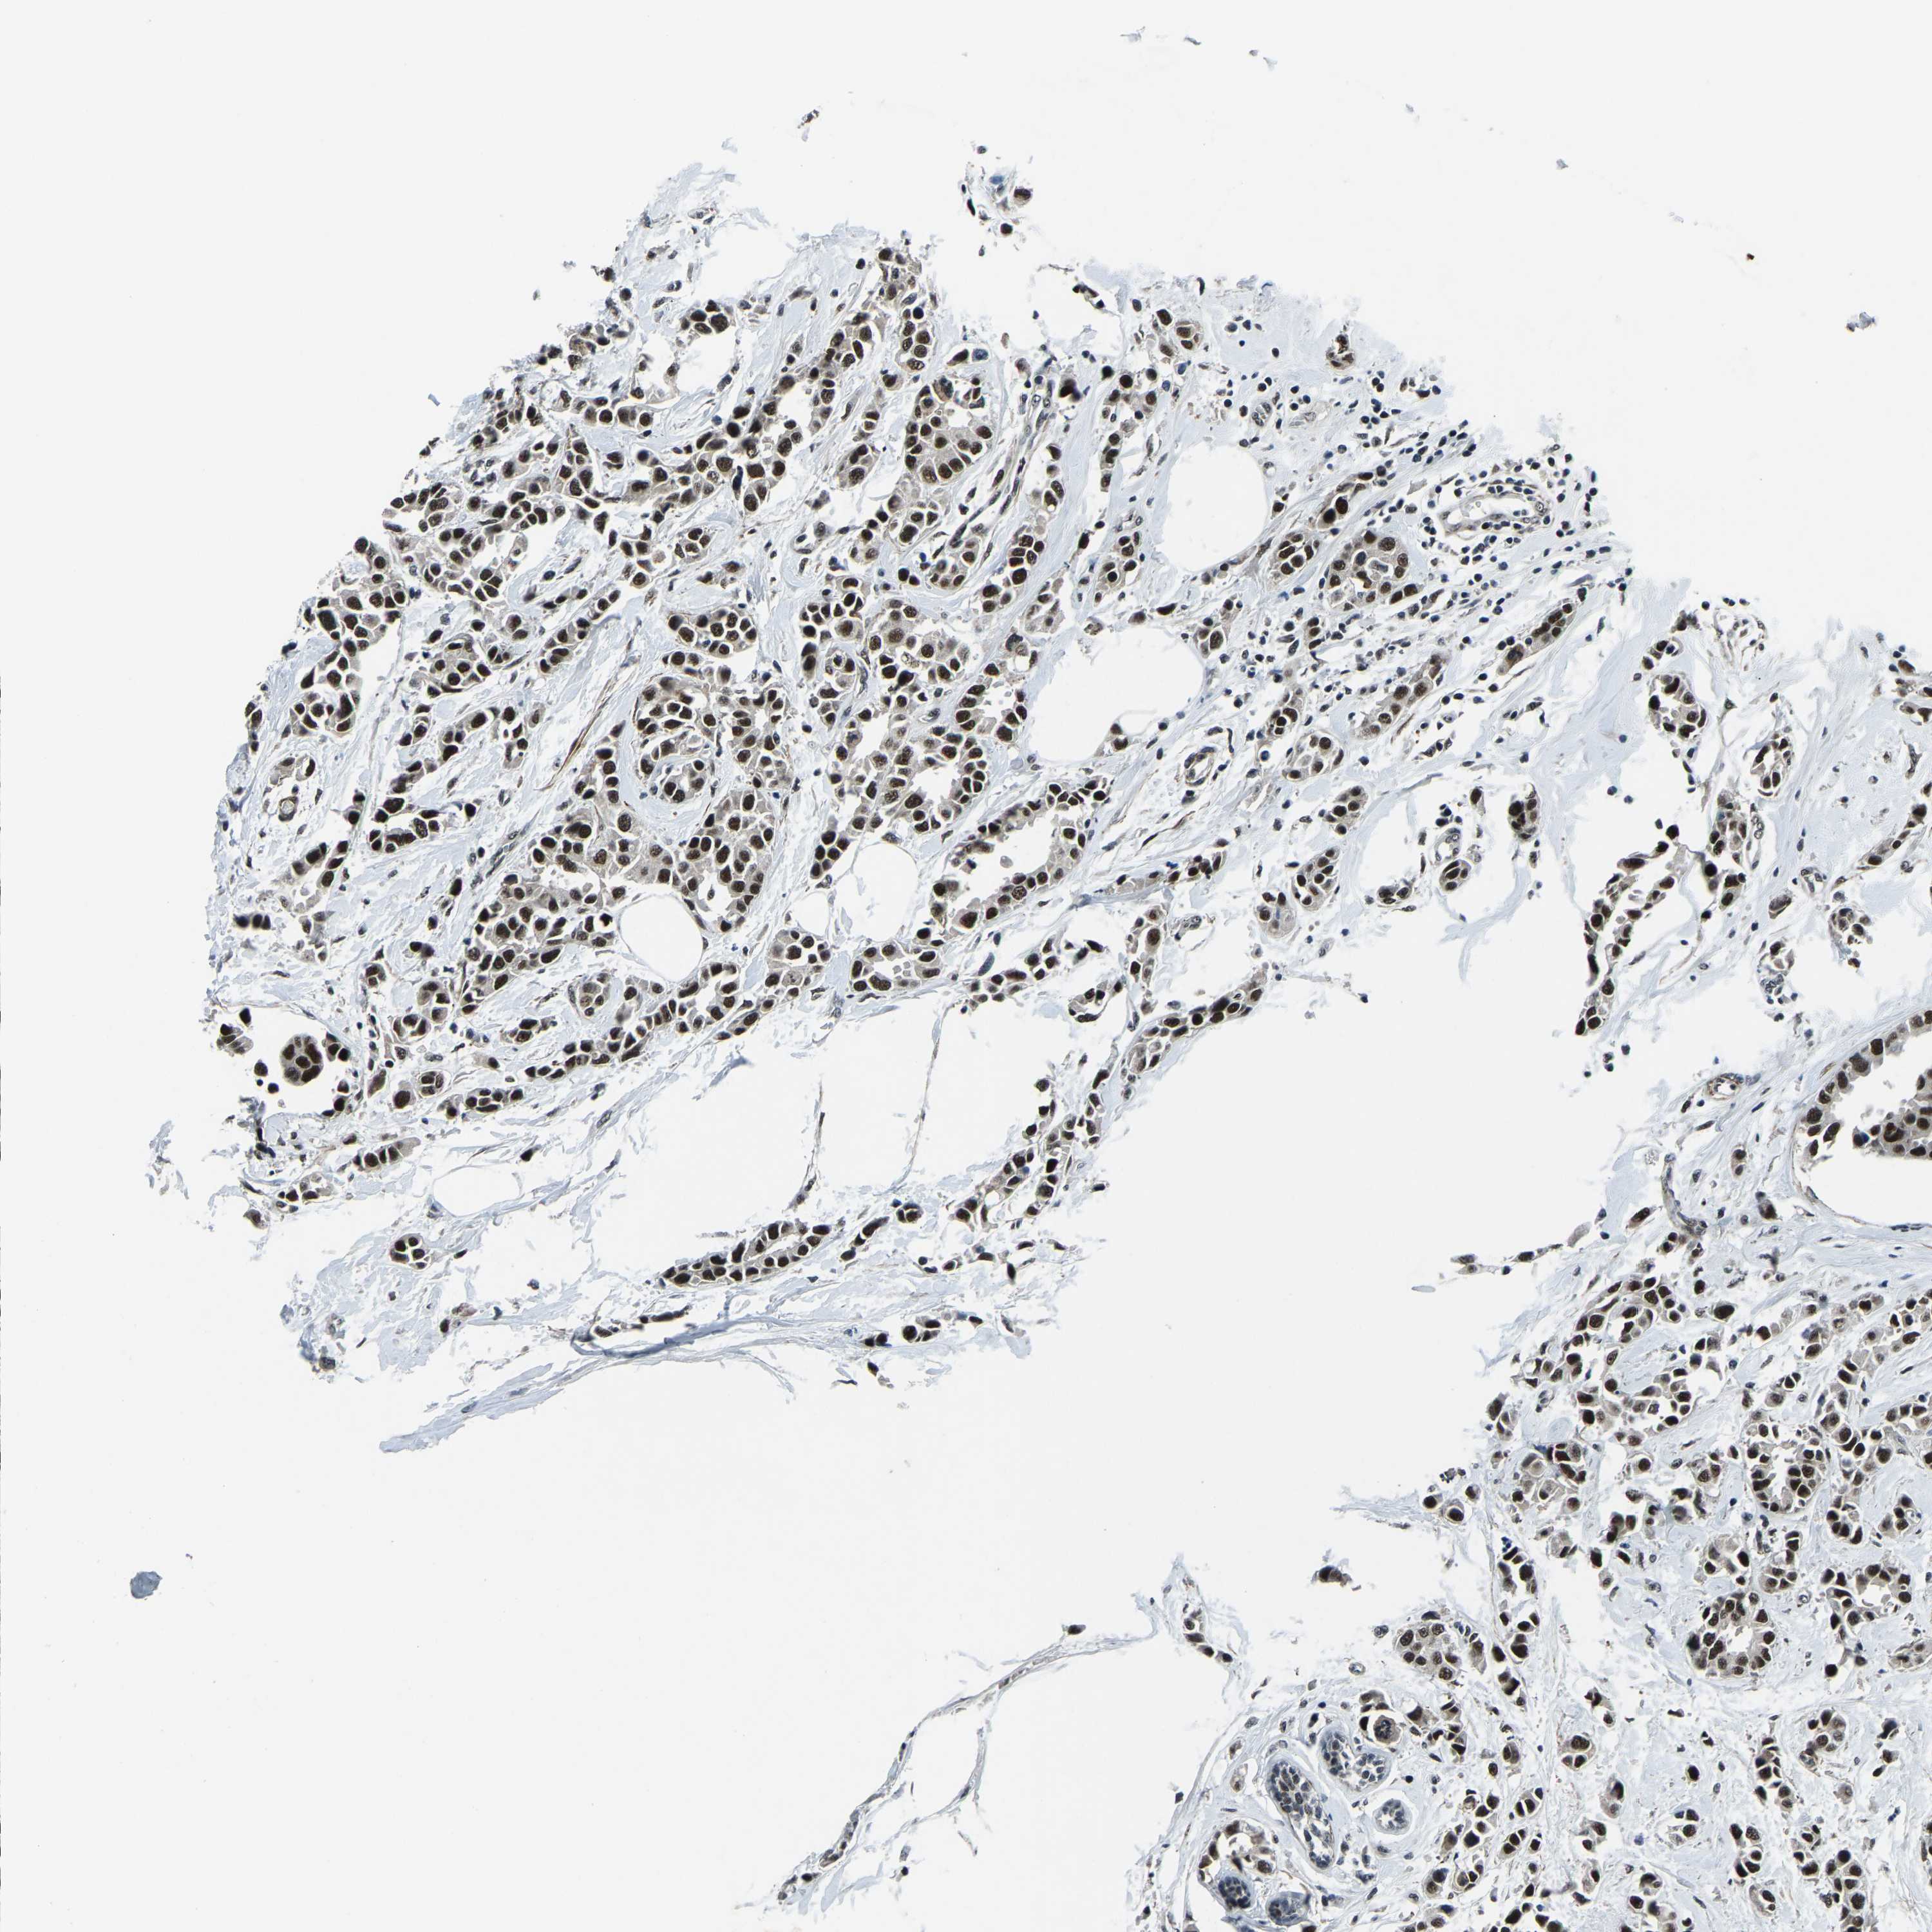

BRCA TCGA BRCA VALIDATION PROTEIN EXPRESSION